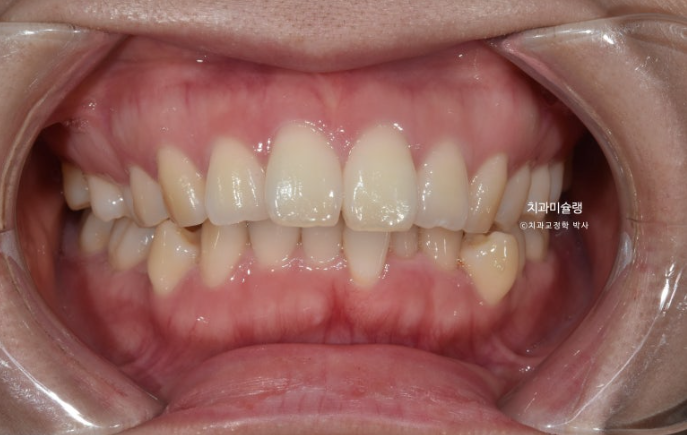

돌출입 교정을 위해 멀리 지방에서 오신 환자분입니다.

윗니 돌출이 심합니다.

아랫니 기준으로 약 1센치가 더 튀어나와 있습니다.

위 아래 앞니 간격은 1-2mm 가 정상입니다.

아래 치열은 덧니가 심한 상황입니다.

골격분석 결과 심한 상악골 전방 돌출을 동반한 골격성 2급 부정교합 입니다.

상악골 과잉에 의한 돌출은 돌출입 교정 중에서도 난이도가 높습니다.

상악과 하악의 골격 부조화가 심해 아래턱이 상대적으로 뒤로 밀려있는 상태여서 위 앞니 각도를 이상적으로 유지하기가 쉽지 않습니다.

입이 안 다물어질 정도의 윗니 돌출과 심한 아래 덧니를 해결하려면 작은어금니 4개 발치는 불가피합니다.